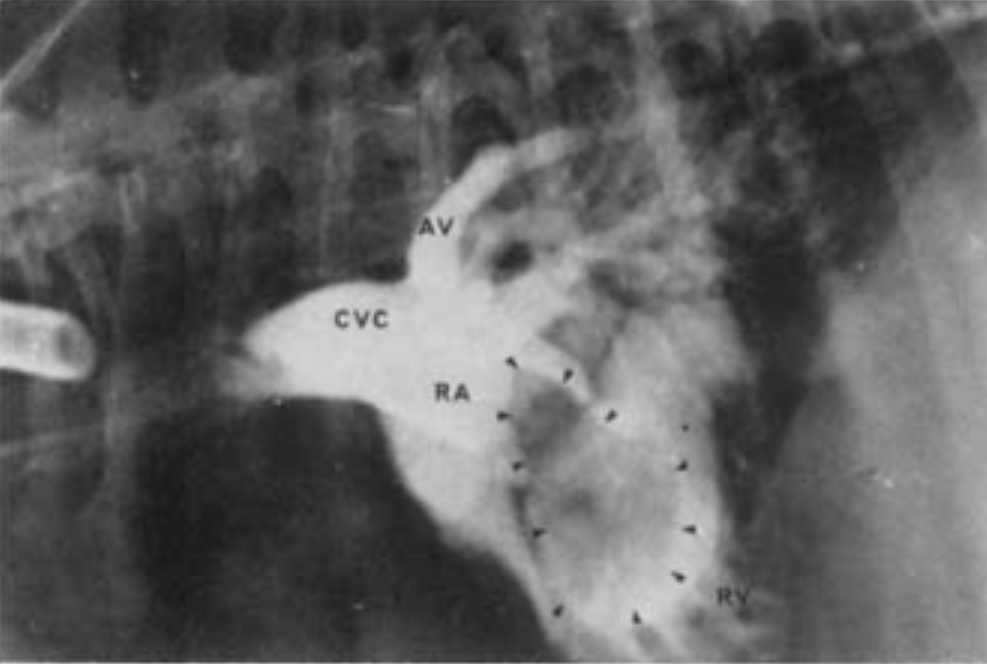

Selective angiography - right atrial injection (normmal dog)

A

RAA = right auricular appendage

RV = right ventricle

PSV = pulmonary sinus of valsalva

MPA = main pulmonary artery

RPA = right pulmonary artery

LPA = left pulmonary artery

Cranial vena caval injection angiogram (dog)

What are the pertinent findings and diagnosis?

Right atrial injection angiocardiogram (dog).